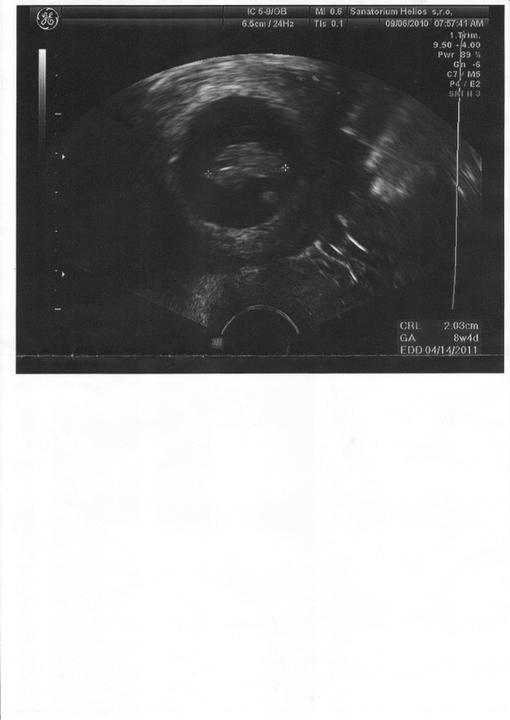

Za 7 hodin uvidíme naši fazolku, nemůžu se dočkat a asi proto nemůžu spát. Strašně se těším. Snad bude vše v pořádku.